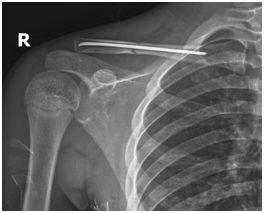

儿童最适合弹性髓内钉治疗

4.手术方法